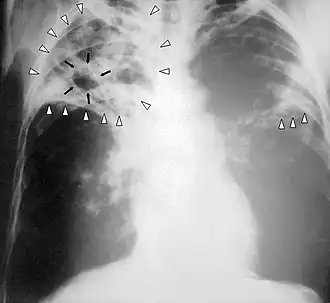

Radiografía de tórax

La radiografía es esencial en el diagnóstico de la enfermedad. Las lesiones típicas radiológicas son apicales, en hemitórax derecho, en segmentos posteriores y en general forman cavidades.